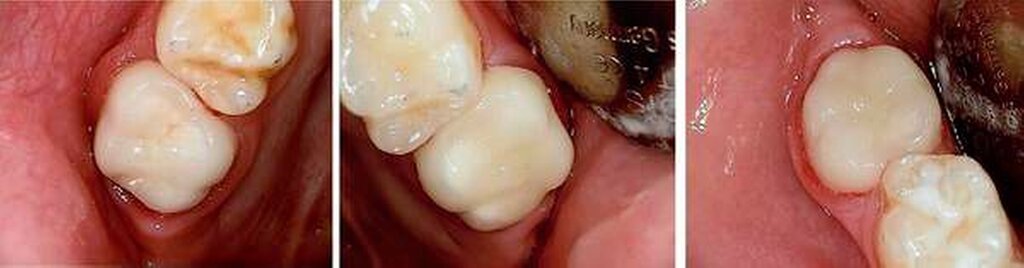

Aufgrund der noch nicht eindeutigen Gebissentwicklung des Patienten und der Tendenz zum Engstand wurde in Absprache mit den Eltern, dem Hauszahnarzt und dem Kieferorthopäden die Entscheidung getroffen, dass die stärker betroffenen und sehr empfindlichen Zähne 26, 36 und 46 mit Stahlkronen versorgt und Zahn 16 neu versiegelt werden sollte (Abbildungen 6 bis 8).

Somit kann die Entscheidung der Extraktionstherapie noch hinausgezögert werden. Sie wird in der Regel vom Kieferorthopäden im Lauf des neunten Lebensjahres des Patienten getroffen. Mit etwa neun Jahren ist die Extraktionstherapie, wenn notwendig, meist am sinnvollsten, da sich zu dieser Zeit der Zahnkeim des zweiten Molaren am günstigsten nach mesial entwickelt. Andernfalls sollte dann, aus parodontalen Gründen, spätestens mit dem 15. Lebensjahr eine definitive Überkronung stattfinden.

Stahlkronen der Sechsjahrmolaren sind ähnlich anzuwenden wie die etwas besser bekannten Stahlkronen im Milchgebiss. Im Gegensatz hierzu ist jedoch auf eine möglichst schonende Präparation zu achten, um genügend Substanz für die spätere definitive Versorgung zu erhalten, die bis zum 15. Lebensjahr erfolgen sollte.

Die konfektionierten Kronen kommen in den Fällen zur Anwendung, wenn die Zähne zumindest über einen gewissen Zeitraum erhalten werden sollen, die Defekte jedoch zu groß für die Füllungstherapie sind.

Leider ist die Präparation der Sechsjahrmolaren oft zeitraubender und geht meist mit erheblichem Substanzverlust einher. Nach versuchter schonender tangentialer Präparation mesial und distal sowie Reduktion der Höhe um circa 1,5 mm wird die entsprechende Kronengröße ausgewählt. Diese kann noch durch Kürzen oder Biegen des Randes individualisiert werden. Wichtig ist es, vor dem definitiven Einsetzen der Kronen den korrekten Sitz mittels Röntgenbild zu überprüfen. Bedingt durch das Fehlen eines basalen Schmelzwulstes lässt sich die Konfektionskrone trotz eines elastischen Federrandes auf dem konisch beschliffenen Zahn nur schwer fixieren. Störungen der Okklusion sind die Norm (noch unproblematisch im beginnenden Wechselgebiss), ein exakter Randschluss ist praktisch nicht zu erreichen. Insbesondere interdental, am Übergang zwischen Krone und Zahn, sind in jedem Fall Retentionsnischen vorhanden, die die Ansammlung von Plaque begünstigen. Folgeproblem ist Sekundärkaries und eine dauerhafte Irritation des marginalen Parodontiums. Verbleiben die Kronen über das 15. Lebensjahr hinaus im Mund, muss mit zum Teil erheblichem Knochenabbau gerechnet werden!